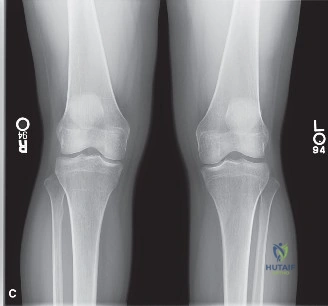

A 22-year-old competitive soccer player presents to your clinic after a non-contact, pivot-shift injury to the left knee. He reports an immediate "pop" and significant swelling. Physical examination reveals a grade III Lachman, positive pivot shift, and a mechanical block to extension. How do you approach this clinical picture?

This is a classic triad presentation. I would proceed with: 1) Clinical assessment to rule out multi-ligament injury (specifically PLC/MCL). 2) Recognize the mechanical block to extension as a clinical indicator of a displaced bucket-handle meniscal tear, which requires timely intervention. 3) Request MRI to define the meniscal pathology and status of the ACL. 4) Counsel the patient on the high risk of further chondral damage if surgery is delayed, and discuss ACL reconstruction with concurrent meniscal repair.

During the arthroscopic reconstruction, you confirm a lateral meniscus bucket-handle tear and an ACL rupture. You also identify a focal 8mm ICRS Grade II chondral defect on the lateral femoral condyle. How do you manage the chondral component?